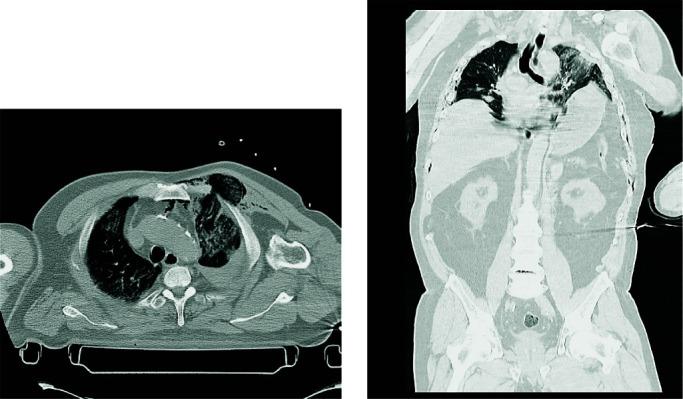

Blunt chest trauma is an important cause of morbidity and mortality in traumatized emergency patients. We report the case of a 74-year-old man who suffered a glenohumeral joint dislocation, trans trochanteric femur fracture, multiple rib fractures, diaphragmatic rupture with chest herniation of the spleen and stomach associated with herniation of the lung through an anterior chest wall defect after blunt trauma. Although immediate surgical repair was performed, he developed a delayed complication of multiple rib fracture in the form of large extrapleural hematoma that had to be surgically removed. Due to massive pulmonary contusion and prolonged pulmonary collapse, we used surfactant to facilitate alveolar opening after evacuation of the hematoma.

钝性胸部创伤是创伤急诊患者发病率和死亡率的重要原因。我们报告了 1 例 74 岁男性患者,该患者因钝性创伤导致肩关节脱位、转子下股骨骨折、多处肋骨骨折、横膈破裂,脾和胃通过前胸壁缺损疝入胸腔,同时肺疝出。尽管立即进行了手术修复,但他出现了多发肋骨骨折的迟发性并发症,表现为巨大的胸腔外血肿,需要手术清除。由于严重的肺挫伤和长时间的肺不张,我们在清除血肿后使用表面活性剂促进肺泡开放。